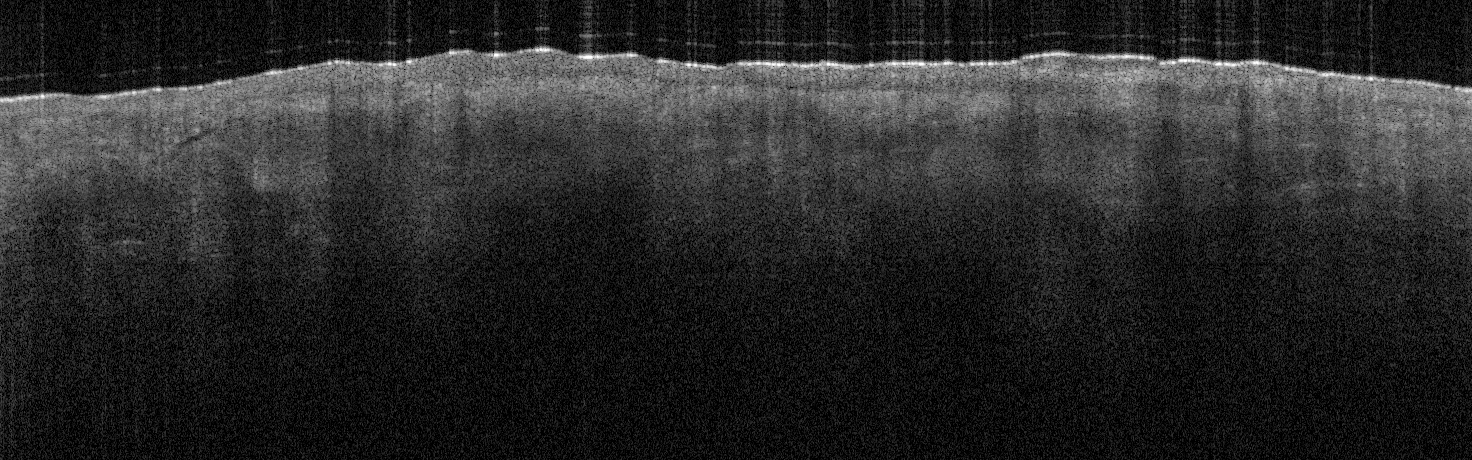

VA35: Left Temple, Actinic Keratosis, Hypertrophic

- White arrows indicate return to dermal collagen texture and reflectivity

VA35: Left Temple, Adjacent, Normal